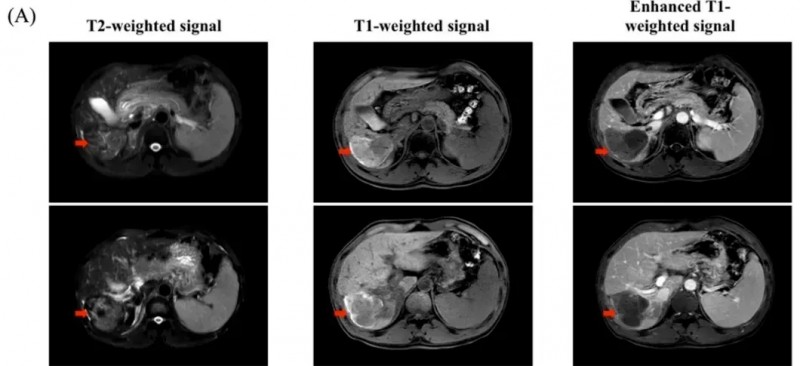

除了C-CAR031的临床数据外,国际知名期刊《Cancer Communications》还报道过我国另一款靶向GPC3的CAR-T细胞疗法案例,该案例中一名肝细胞癌患者实现了长达8年的无癌生存。这名患者为50岁男性,既往患有乙型肝炎肝硬化,后确诊为Ib期肝细胞癌。他曾接受过2次化疗、微波消融术等多种治疗,但效果不佳,肿瘤持续进展,遂入组接受CAR-GPC3T细胞治疗。

结果显示:接受CAR-GPC3T细胞治疗6个月后,影像学检查提示肿瘤迹象消失,肿瘤标志物AFP(甲胎蛋白)也恢复正常。更令人惊喜的是,截至报道时,该患者已无癌生存长达8年(2015年7月~2023年8月),并逐步回归了正常生活。

▲图源“Cancer Commun”,版权归原作者所有,如无意中侵犯了知识产权,请联系我们删除